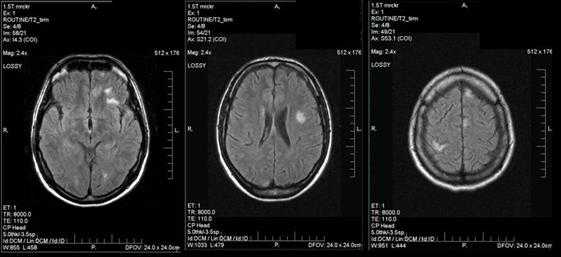

Органическое поражение ЦНС выявлено лишь у 1 (1,2%) пациента при длительном течении ИКБ (около 2-х лет) при отсутствии своевременной верификации диагноза, а следовательно, адекватной этиопатогенетической терапии. Клинические проявления характеризовались постоянной головной болью на фоне субфебрильного повышения температуры тела, снижением памяти, концентрации внимания. По результатам МРТ головного мозга выявлены мультифокальные очаги преимущественно белого вещества обоих полушарий и левой гемисферы мозжечка (рис. 2). В результате этиопатогенетической терапии клиническая симптоматика регрессировала, согласно результатам МРТ головного мозга, проведенного через 6 месяцев, количество очагов поражения белого вещества уменьшилось.

Рисунок 2. МРТ головного мозга - очаговое поражение головного мозга

при хроническом нейроборрелиозе